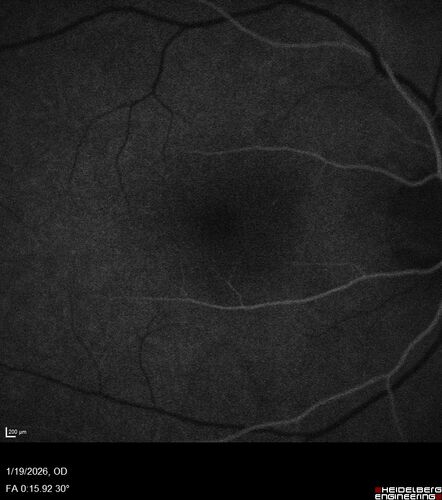

Acute Retinal Pigment Epitheliitis (Krills disease)

15 year old with sudden central vision loss in one eye.  The vision loss persisted though for at least 6 months (which may be a laser injury)